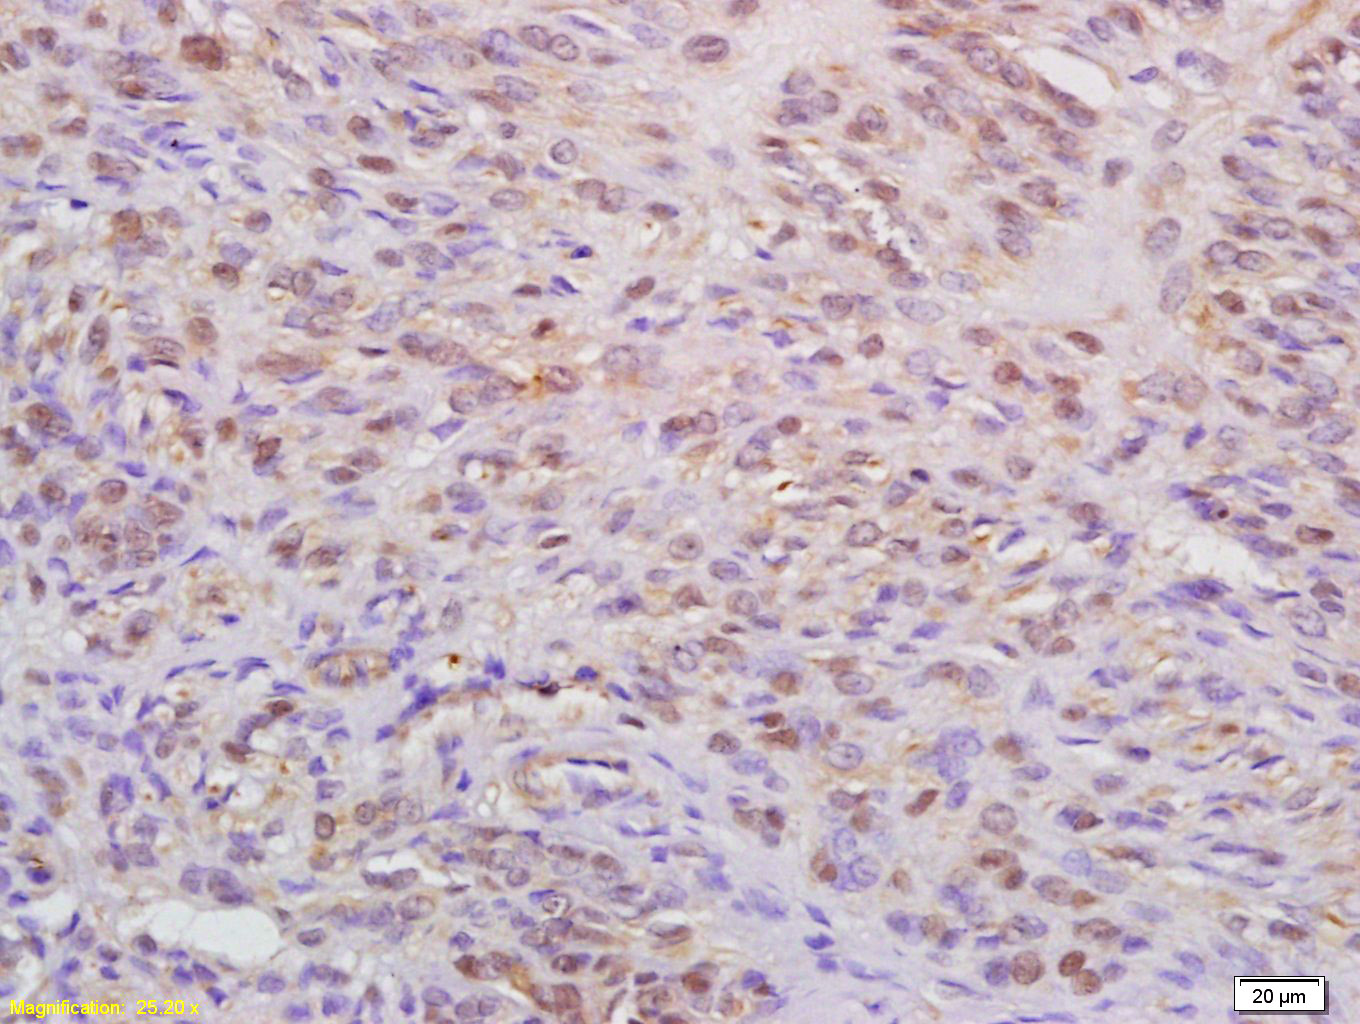

Antigen retrieval: citrate buffer ( 0.01M, pH 6.0 ), Boiling bathing for 15min; Block endogenous peroxidase by 3% Hydrogen peroxide for 30min; Blocking buffer (normal goat serum,C-0005) at 37℃ for 20 min;

Incubation: Anti-WAPL Polyclonal Antibody, Unconjugated(bs-7733R) 1:200, overnight at 4°C, followed by conjugation to the secondary antibody(SP-0023) and DAB(C-0010) staining